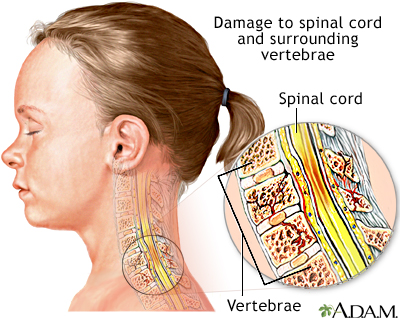

The spinal cord contains the nerves that carry messages between your brain and the rest of your body. The cord passes through your neck and back. A spinal cord injury is very serious because it can cause permanent loss of movement (paralysis), function, and sensation below the site of the injury.

- Fracture of the spine

- Traumatic injury to the face, neck, head, chest, or back (for example, a car accident)